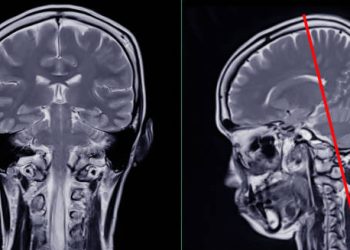

Diagnosis of Chiari Malformation Diagnosis of Chiari malformation...